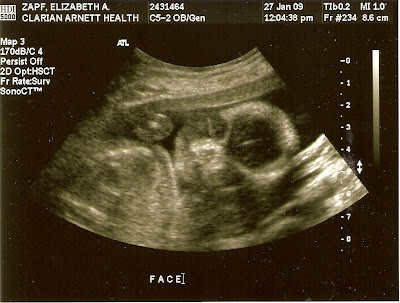

So, here is “New Baby” at 20 weeks:

I didn’t add any captions because the ultrasound tech did such a lovely job of it, I didn’t want to attempt to out-do her.